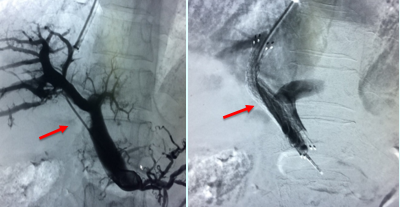

直接TIPS+支架压迫血栓 (肝硬化基础PVT)

血栓抽吸、扩张后行TIPS(肝硬化基础PVT)